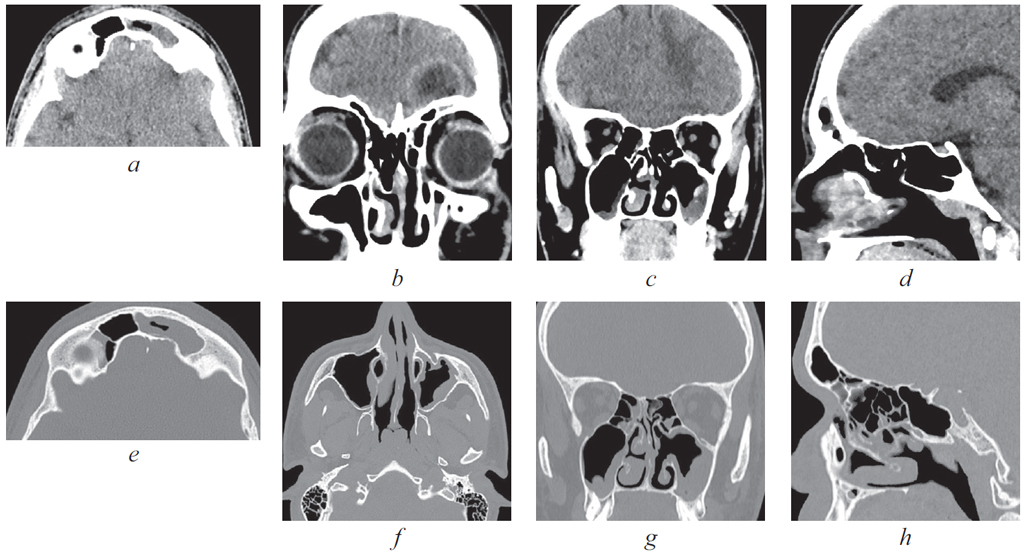

По результатам КТ ОНП от 08.11.2021: правосторонний сфеноидит с уровнем жидкости, левосторонний верхнечелюстной синусит с уровнем жидкости (рис. 4–6).

Рис. 4. Компьютерная томография околоносовых пазух и головного мозга от 08.11.2021: аксиальная проекция в режиме skull. Тотальное затенение правой половины пазухи клиновидной кости справа, уровень жидкости в левой верхнечелюстной пазухе

Fig. 4. Computed tomography of the paranasal sinuses and brain from 08.11.21: axial projection in skull mode. Total shading of the right half of the sphenoid sinus on the right, fluid level in the left maxillary sinus

Рис. 5. Магниторезонансная томография головы от 10.11.2021: правосторонний сфеноидит, тромбоз кавернозного синуса слева. Слева — коронарная проекция в режиме Т2. Тотальное затенение правой половины пазухи клиновидной кости, сужение кавернозного синуса слева; справа — аксиальная проекция в режиме Т2. Признаки тромбоза кавернозного синуса слева

Fig. 5. Magnetic resonance imaging of the head from 10.11.2021: right-sided sphenoiditis, thrombosis of the cavernous sinus on the left. Left: coronal projection in T2 mode. Total shading of the right half of the sphenoid sinus, narrowing of the cavernous sinus on the left; right: axial projection in T2 mode. Signs of thrombosis of the cavernous sinus on the left

Рис. 6. Магнитно-резонансная томограмма головного мозга. Признаки тромбоза кавернозного синуса. 1 — Венозный застой в ретробульбарной клетчатке; 2 — cужение просвета сифона внутренней сонной артерии слева; 3 — неоднородность структуры

Fig. 6. Signs of cavernous sinus thrombosis on magnetic resonance imaging of the brain. 1 — Venous congestion in the retrobulbar tissue; 2 — narrowing of the lumen of the siphon of the internal carotid artery on the left; 3 — structure heterogeneity